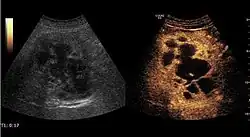

It is the most common liver tumor with a prevalence of 0.4 – 7.4%. It is generally asymptomatic but also can be associated with pain complaints or cytopenia and/or anemia when it is very bulky. It is unique or paucilocular. It can be associated with other types of benign liver tumors. Characteristic 2D ultrasound appearance is that of a very well defined lesion, with sizes of 2–3 cm or less, showing increased echogenity and, when located in contact with the diaphragm, a "mirror image" phenomenon can be seen. When palpating the liver with the transducer the hemangioma is compressible sending reverberations backwards. Doppler exploration reveals no circulatory signal due to very slow flow speed. CEUS investigation has real diagnosis value due to the typical behavior of progressive CA enhancement of the tumor from the periphery towards the center. The enhancement is slow, during several minutes, depending on the size of hemangioma and on the presence (or absence) of internal thrombosis. During late (sinusoidal) phase, if totally "filled" with CA, hemangioma appears isoechoic to the liver. Deviations from the above described behavior can occur in arterialized hemangiomas or those containing arterio-venous shunts. In these cases, differentiation from a malignant tumor is difficult and requires other imaging procedures, follow up and measurements of the tumor at short time intervals.[4]